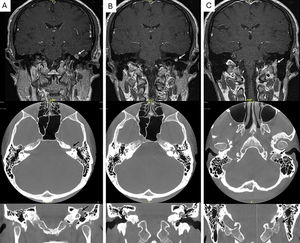

RM secuencia T1 con gadolinio, plano coronal (fila superior), y TC en plano axial (fila media) y coronal (fila inferior). Se demuestra la presencia de una lesión (flecha) fusiforme que depende del nervio facial y presenta un carácter expansivo, esta es isointensa en la RM bajo secuencia T1. La lesión se extiende desde el ganglio geniculado A), afectando a la segunda porción del nervio facial, B) así como a la tercera porción extendiéndose a través del agujero estilo-mastoideo. C) No hay afectación a nivel del ángulo pontocerebeloso o del canal auditivo interno. El hallazgo es compatible con un schwannoma del nervio facial.

Un varón de 48 años refirió hipoacusia en el oído izquierdo y un acúfeno incapacitante ipsilateral de un año de evolución. Tenía antecedente de una parálisis de Bell izquierda (una década antes), tras la que quedaron sincinesias ipsilaterales ocasionales que se intensificaron en los últimos meses. La audiometría mostró una caída conductiva leve y bilateral en graves, mientras que a la otoscopia se apreció la ocupación de oído medio izquierdo por una masa grisácea. La movilidad facial estaba conservada (House-Brackmann [H-B] grado I). Las pruebas de imagen del hueso temporal (tomografía computarizada [TC] y resonancia magnética [RM]) fueron compatibles con un schwannoma del nervio facial (SNF) izquierdo con afectación temporal y extratemporal (fig. 1). En ese momento, dadas la función facial conservada y la ausencia de complicaciones, se optó por un seguimiento clínico-radiológico estrecho.